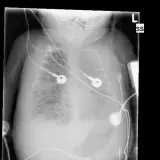

Over 2,100 interactive radiology cases, curated by radiologists for your level of training. Scroll, window, and view cases full screen — just like on PACS. Click linked findings in each writeup to jump straight to them on the image. Cases include sample reports, a focused discussion section, original illustrations, and videos.

完全交互式病例,配备您在 PACS 上期待的各项工具——滚动、调窗、缩放、平移、测量、ROI 和全屏模式。

丰富的标注直接在病例图像上突出关键发现。点击病例讲解中的关联发现,即可跳转至其在扫描上的精确位置。